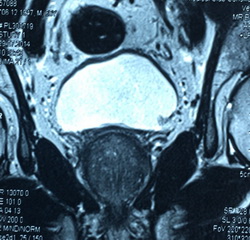

Из анамнеза: в июле 2014 года после физической нагрузки отметил появление крови в моче с бесформенными сгустками. В поликлинике по месту жительства при ультразвуковом исследовании выявлена аденома предстательной железы. Консультирован в клинике урологии УКБ№2 Первого МГМУ им. И.М. Сеченова, при УЗИ заподозрена опухоль мочевого пузыря. Выполнена МРТ органов малого таза, по данным которой по левой боковой стенке мочевого пузыря определяется экзофитное образование размерами 0,9х0,8х0,7мм. Также выявлена аденома предстательной железы. Госпитализирован в плановом порядке для оперативного лечения

Рис№2 Магнитно резонансная томография органов малого таза